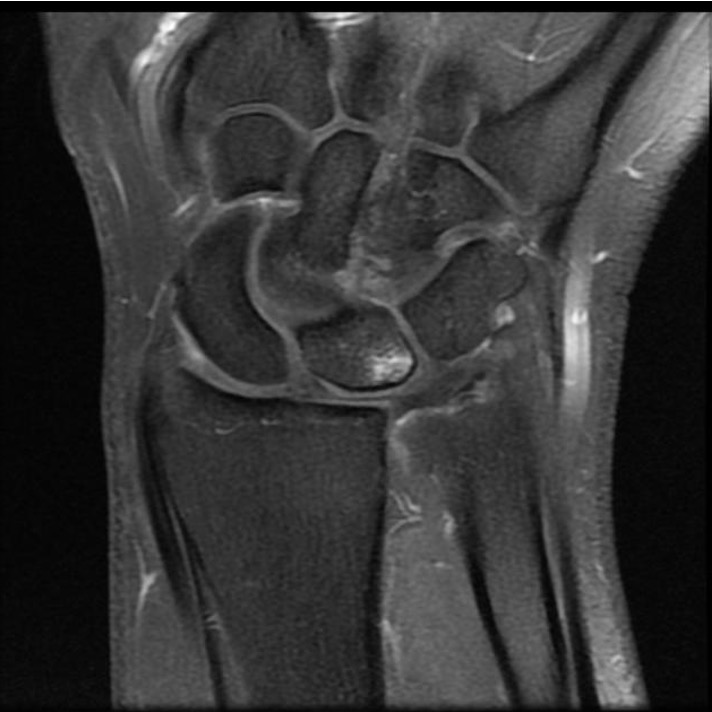

Ulno-carpal abutment

Ulnocarpal abutment and lunate chondromalacia

Ulna positive with ulnocarpal osteoarthritis

Class 2 Degenerative TFCC tears

Central TFCC tear with ulna positive variance an ulnocarpal abutment on MRI

Background

Ulna impaction syndrome / Ulno-carpal abutment

Progression of wear

- TFCC thinning

- ulna head and lunate cartilage wear

- TFCC perforation

- lunate-triquetral ligament injury

- ulnocarpal osteoarthritis

Usually associated with ulna positive variance and treated with ulna shortening